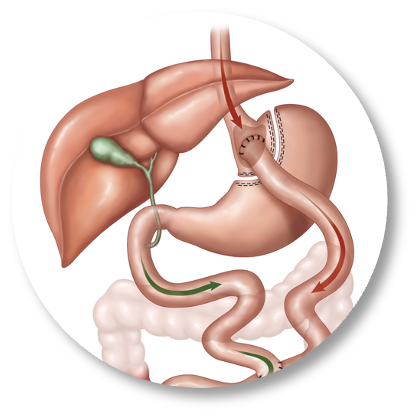

The first cut-free endoscopic treatment for diabesity, ForePass ® is able to replicate the most common types of metabolic surgery (Roux-en-Y Gastric Bypass, RYGB, BilioPancreatic Diversion, and Sleeve Gastrectomy). The first version of our product is aimed at RYGB.

Designed to replicate metabolic surgery without any cuts to internal organs. As effective on diabetes and obesity as metabolic surgery in animals.

ForePass ® replicates the three most common metabolic surgeries without requiring a single cut